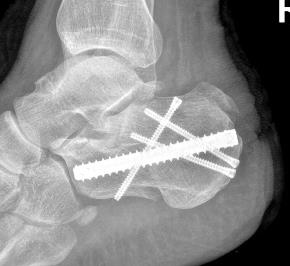

• 关节镜技术联合钉中钉系统全内修复跟骨关节内骨折的临床疗效观察

2026, 32(1):19-25. DOI: 10.12235/E20250392

摘要 (74) HTML (35) PDF 2.90 M (82) 评论 (0) 收藏

摘要:目的 探讨关节镜技术联合钉中钉系统全内修复跟骨关节内骨折的临床疗效。方法 回顾性分析2021年5月-2024年4月该院骨与关节康复科收治,并获得随访的31例闭合性跟骨关节内骨折患者的临床资料。均采取关节镜技术联合钉中钉系统全内修复手术治疗方案。术前及术后均行跟骨侧轴位X线片及足部CT检查,根据影像学结果对骨折类型进行分型,并评价术后骨折复位情况。比较手术前后跟骨高度、宽度、Bohler角和Gissane角。记录术前等待时间、手术时间、术中出血量、住院时间、术后疼痛视觉模拟评分法(VAS)评分等围手术期相关指标及术后并发症发生情况。采用美国足踝外科协会(AOFAS)评分和Maryland足部评分评估临床疗效。结果 术后影像学检查,可见跟骨术后关节面塌陷骨块复位;跟骨高度明显高于术前,跟骨宽度明显窄于术前,Bohler角较术前明显增大,Gissane角较术前明显缩小,差异均有统计学意义(P < 0.05)。术前等待时间为6(4,7)d,手术时间为(188.77±39.53)min,术中出血量为(59.03±23.00)mL,住院时间为(16.49±4.04)d,术后疼痛VAS评分为2(1,2)分,AOFAS评分为92(90,95)分,Maryland评分为92(90,95)分。结论 采用关节镜技术联合钉中钉系统全内修复跟骨骨折,具有可早期开展手术、创伤小、直视下复位、固定可靠和无切口相关并发症等优点,适用于Sanders Ⅱ型和Ⅲ型跟骨骨折。值得应用于临床。